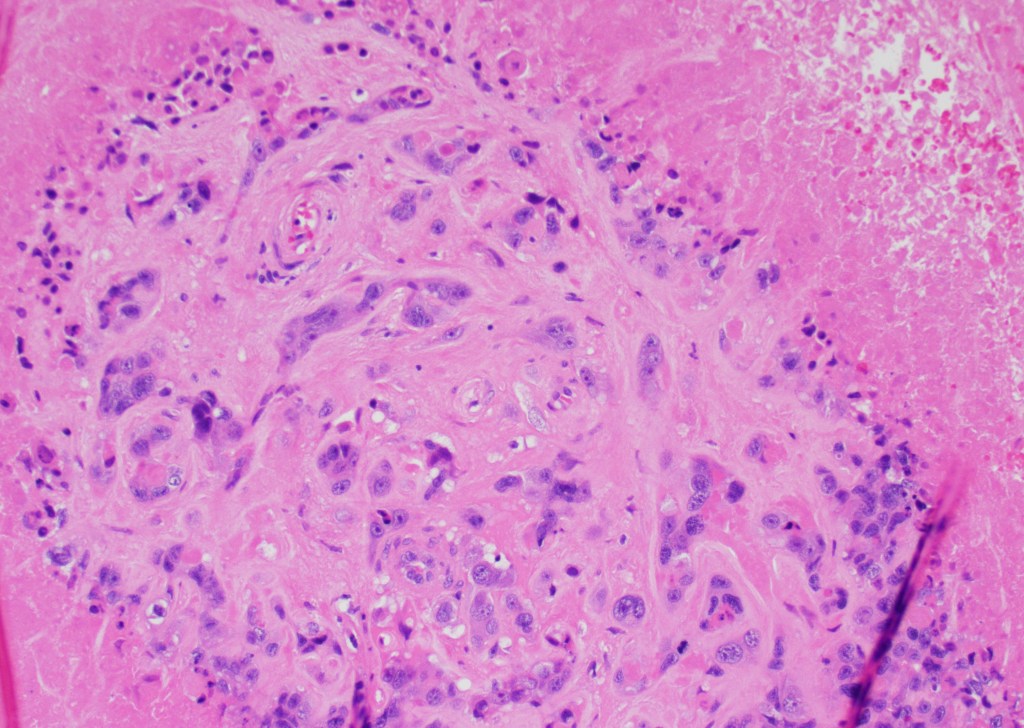

Microscopic examination: the lesion revealed nodular, expansile growth. The nodules were composed of epithelioid cells with abundant eosinophilic cytoplasm, frequent mitotic figures, and the background of necrosis. The nodules and the cells were embedded in the background of hyaline material (Figures 1-4). The cells were positive for GATA-3, alpha inhibin, cytokeratin, and negative for ER, PR, beta-hCG, p16, p53. The diagnosis of the epithelioid trophoblastic tumor (ETT) was rendered. Two years later she presented with new lung nodules. The biopsy showed a metastatic epithelioid trophoblastic tumor with the same immunophenotype. Immunohistochemistry for PD-L1 was positive.

Figure 3

Grossly, the tumor is a distinct lesion or a mass (required for the diagnosis). Microscopically, the cells grow in a nodular pattern with pushing invasion into adjacent structures. The neoplastic cells are large with abundant cytoplasm, arranged in nests and sheets. The mitotic rate is variable, and it ranges from <10 per 10 high-power fields to brisk mitotic activity. High mitotic count is a poor prognostic sign. The background of eosinophilic hyaline-like material is frequently present. Many times, like in our example, extensive geographic necrosis is noted.

Calcifications, when seen, are somewhat unique for epithelioid trophoblastic tumors (usually not seen with placental site of trophoblastic tumor or choriocarcinoma). Clinically, these tumors can have a low level of beta-hCG; however, the increase in beta-hCG is never as high as in choriocarcinoma. The differential diagnosis includes placental site trophoblastic tumor (PSTT), placental site nodule (PSN), keratinizing squamous cell carcinoma of the cervix (SCC), and epithelium smooth muscle tumors (SMT) and PEComa’s, especially on the small biopsies.